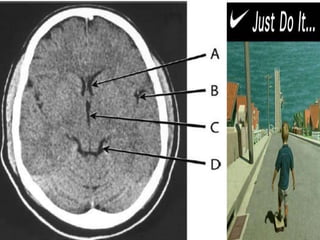

Right and left sylvian fissures (black arrows)

meeting at the suprasellar cistern.

A = Left

frontal horn

B = Left

sylvian fissure

C = Third

ventricle

D = Ambient

cistern